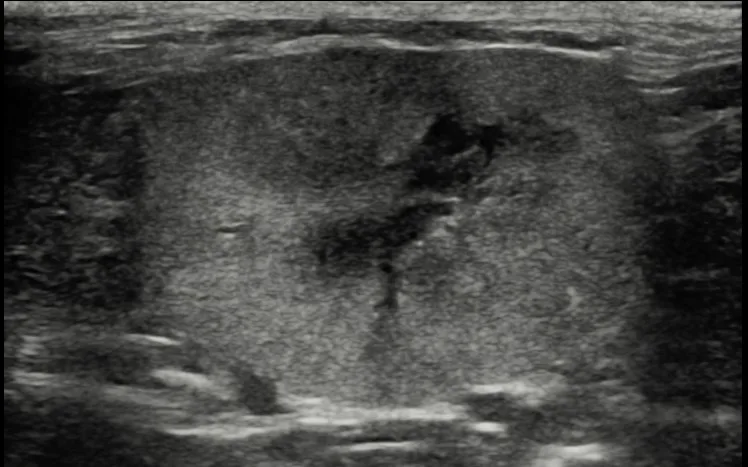

Mucous membranes are pink and moist with a normal capillary refill time (<2 seconds). Heart rate is 180 bpm, respiratory rate is 24 breaths per minute, and rectal temperature is 101.1°F (38.4°C). Thoracic auscultation is unremarkable, and both kidneys are subjectively small on abdominal palpation. Indirect ophthalmoscopy reveals diffusely tortuous retinal vessels with bilateral bullous retinal detachments (Figure 1). Systolic blood pressure (SBP) obtained via Doppler sphygmomanometry is 170 mm Hg (Table). Serum chemistry profile reveals a creatinine of 2.5 mg/dL (reference interval, 0.23-2 mg/dL), BUN of 33.6 mg/dL (reference interval, 7-27.7 mg/dL), and phosphate of 6.9 mg/dL (reference interval, 2.8-6.8 mg/dL); no other abnormalities are seen.

FIGURE 1 Tortuous retinal vessels with bullous retinal detachments in a cat with systemic hypertension